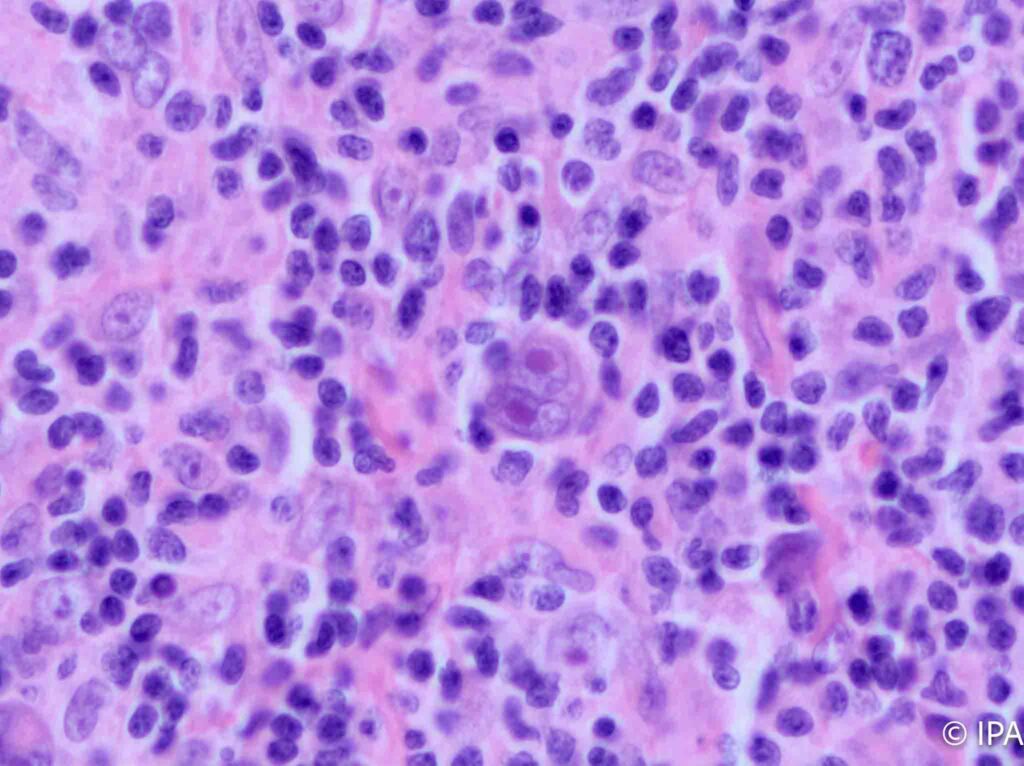

- Hematopatología y Partes Blandas: Diagnóstico de linfomas y sarcomas de alta complejidad.